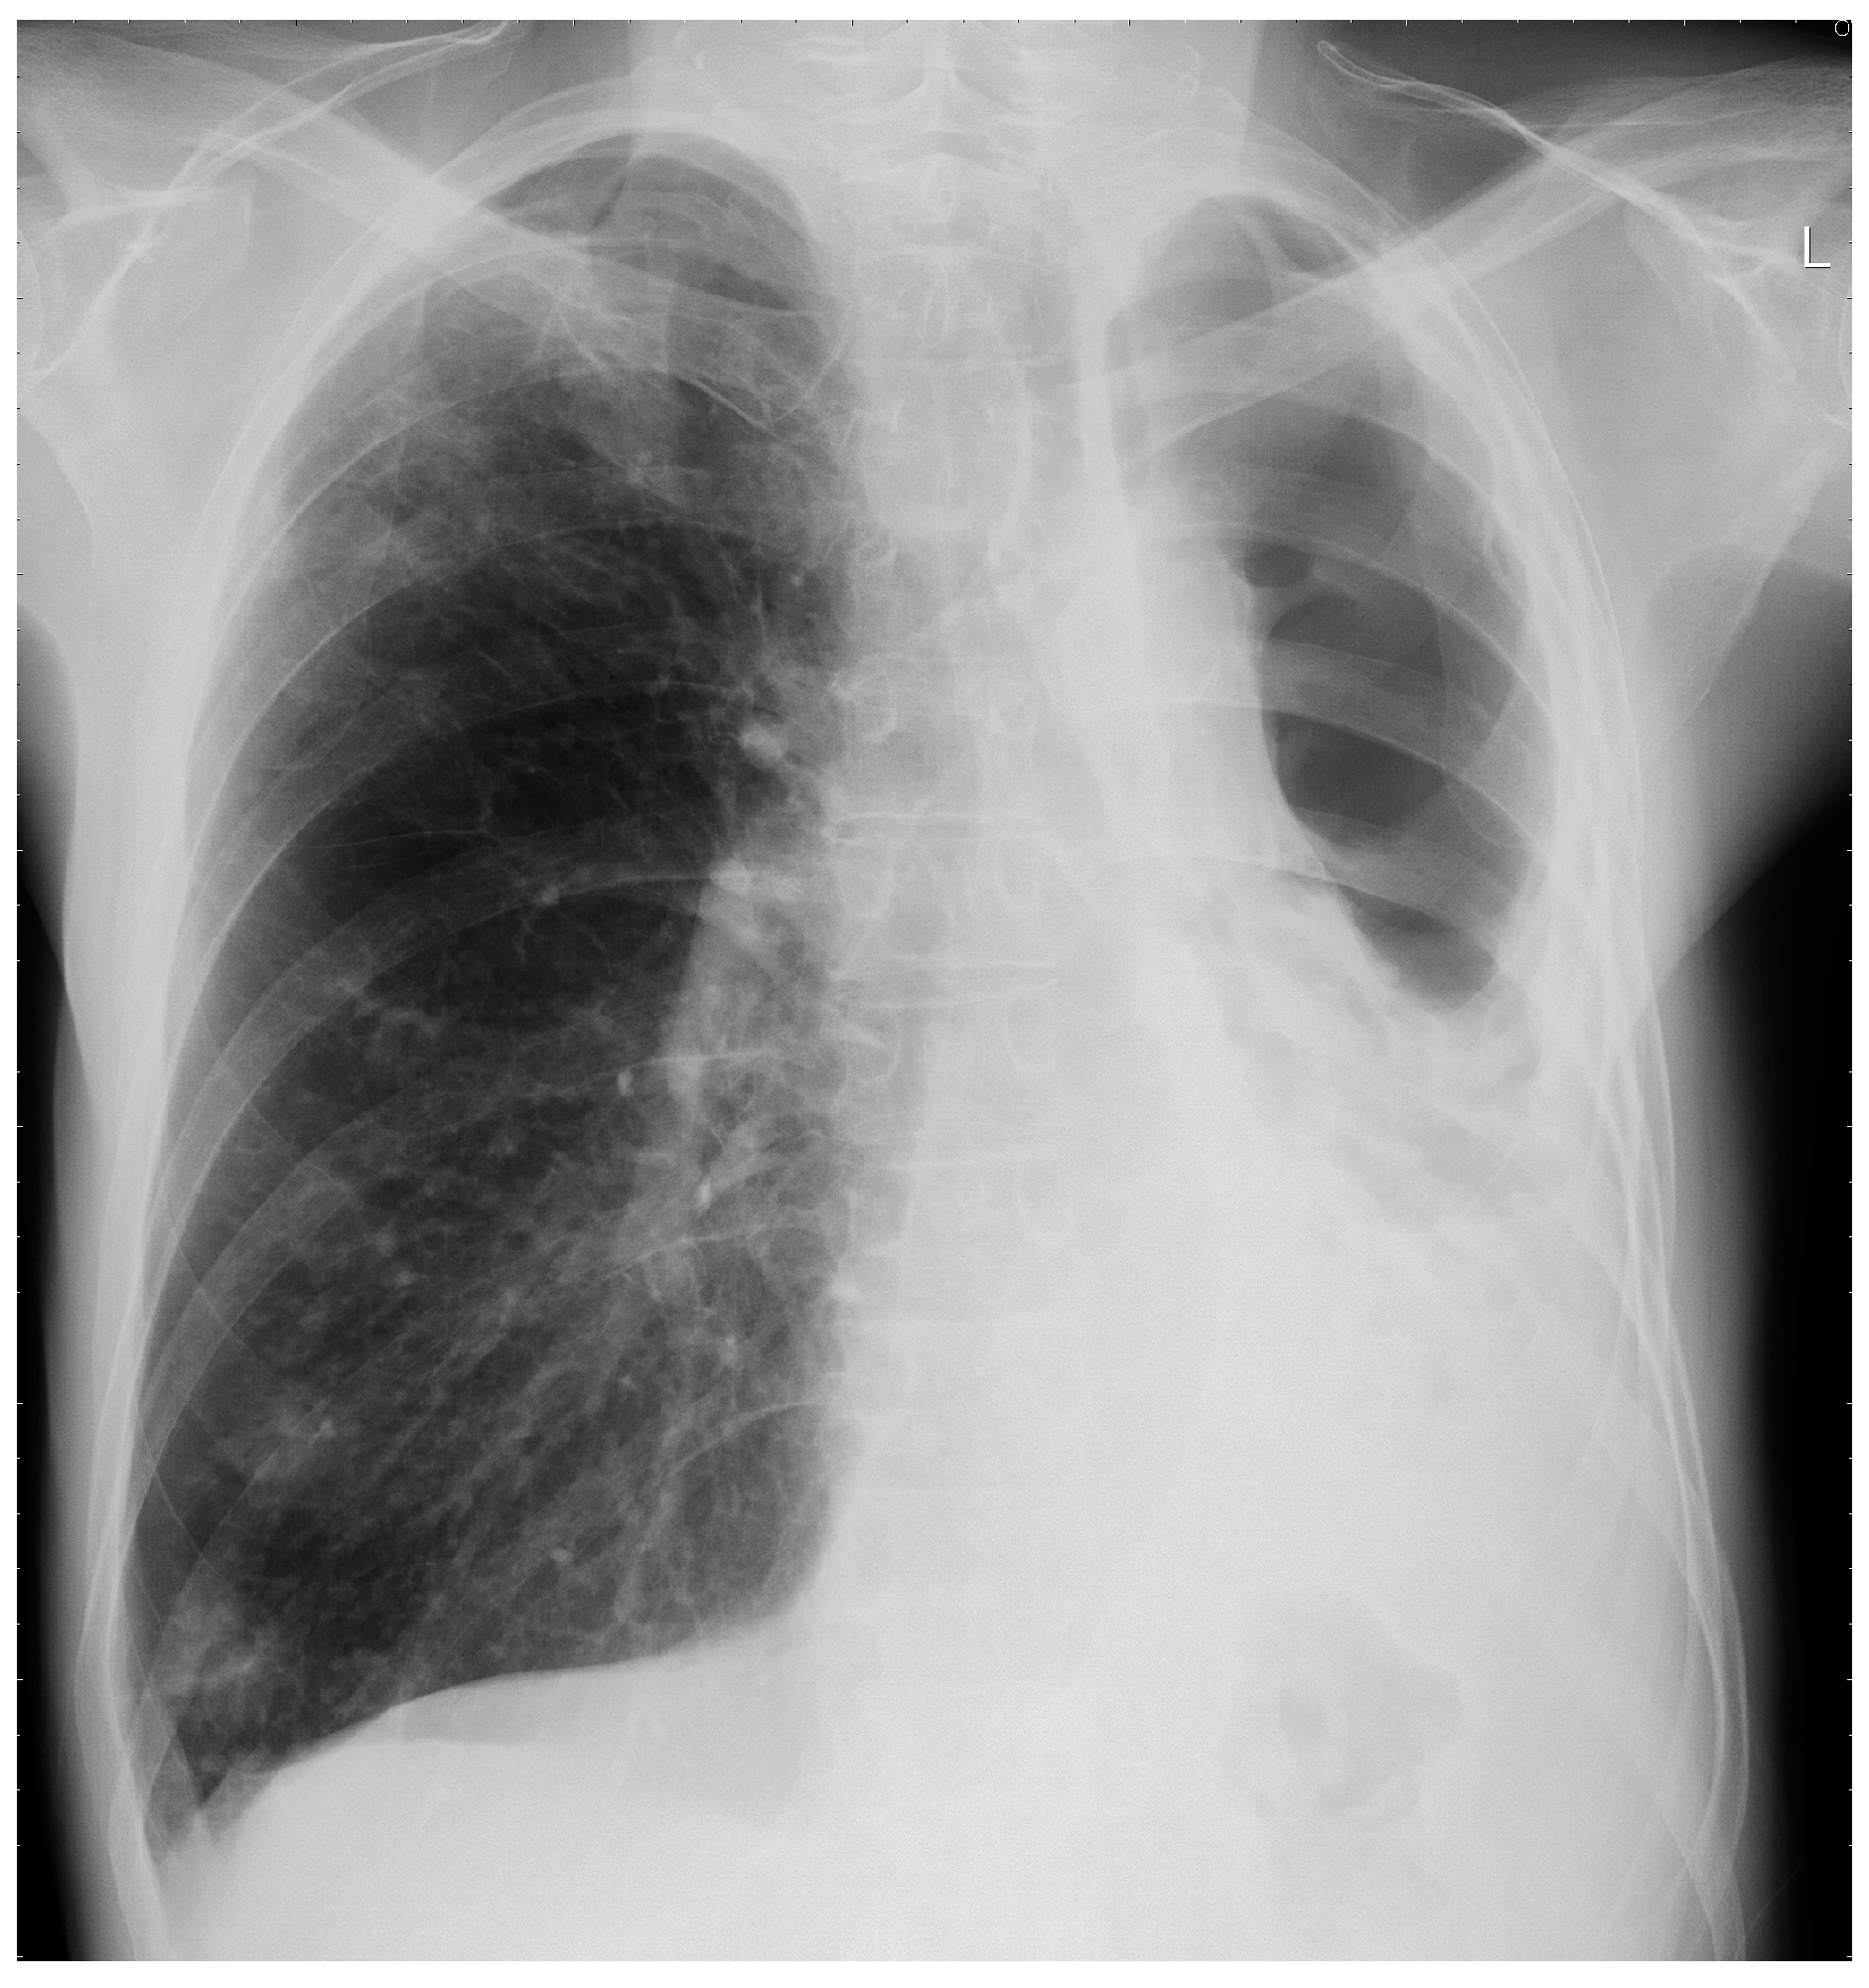

4.2. Radiology

- Desai, S.R.; Hedayati, V.; Patel, K.; Hansell, D.M. Chronic aspergillosis of the lungs: Unravelling the terminology and radiology. Eur. Radiol. 2015, 25, 3100–3107. [Google Scholar] [CrossRef] [PubMed]

- Franquet, T.; Muller, N.L.; Gimenez, A.; Guembe, P.; de La Torre, J.; Bague, S. Spectrum of pulmonary aspergillosis: Histologic, clinical, and radiologic findings. Radiographics 2001, 21, 825–837. [Google Scholar] [CrossRef] [PubMed]

- Greene, R. The radiological spectrum of pulmonary aspergillosis. Med. Mycol. 2005, 43, S147–S154. [Google Scholar] [CrossRef] [PubMed]